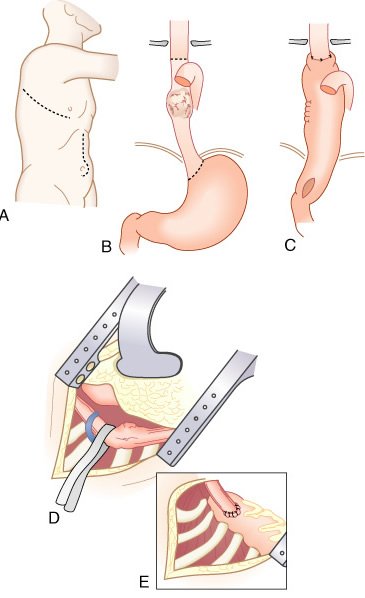

Mobilização do estômago para derivação gástrica subesternal ou substituição esofágica após esofagectomia transiatal. Os vasos gástricos e gastroepiplóicos direitos são preservados, a manobra de Kocher e a piloromiotomia realizadas, e a cárdia seccionada com grampeador e reforço manual. A esofagectomia transiatal é realizada através de uma laparotomia mediana supraumbilical e uma incisão cervical sem toracotomia; entretanto, o esôfago torácico é ressecado atravês da ampliação do hiato diafragmático e do pescoço. O estômago é mobilizado pela secção dos vasos gastroepiplóicos esquerdos e gástricos esquerdos, com preservação das arcadas gastroepiplóica direita e gástrica direita.

Mobilização esofágica durante esofagectomia transiatal sob visualização direta, auxiliada pela ampliação do hiato diafragmático e retração anterior das estruturas mesomediastinais Piloromiotomia e jejunostomia alimentar são realizadas de rotina. Todo o esôfago torácico, do nível das clavículas à cárdia, é ressecado, enquanto há monitoração cuidadosa da pressão intra-arterial para evitar hipotensão prolongada pela mobilização cardíaca durante a dissecção esofágica transiatal .

Após completar a esofagectomia transiatal para tumor localizado no terço distai, é confeccionado o tubo gástrico com o emprego de grampeamento mecânico da grande curvatura, ressecando o máximo de estômago possível distai ao tumor macroscópico. O restante do estômago é, então, posicionado no mediastino posterior no leito esofágico original e anastomosado ao esôfago cervical O grampeador cirúrgico é utilizado para a confecção do tubo gástrico a partir da grande curvatura gástrica com preservação de todo o comprimento.

Após a esofagectomia transiatal e a piloromiotomia, o estômago é mobilizado através do mediastino posterior, o fundo suturado à fascia cervical pré-vertebral, e a esofagogastrostomia término-lateral é, então, realizada

O grampeador é fechado, com aproximação das pás; mas, antes de dispará-lo, realizam-se dois pontos de suspensão em cada lado, entre o estômago anterior e o esôfago adjacente. B, Quando a lâmina do grampeador é avançada, a "parede comum" entre o esôfago e o estômago é seccionada, criando-se uma anastomose ipsilateral de 3 cm de extensão. Então, a sutura dos ângulos é feita em cada lado da gastrotomia. C, A gastroto-mia e o esôfago aberto remanescente são aproximados em duas camadas

O estômago é mobilizado através do mediastino posterior no leito esofagico original e anastomosado (manual ou por grampeamento) ao esôfago cervical.

O estômago normal, adequadamente mobilizado, alcança o pescoço em todos os pacientes.

Esofagectomia torácica total e gastrectomia parcial proximal realizada para adenocarcinoma limitado à junção gastroesofágica e estômago adjacente. Tais tumores podem ser ressecados com uma margem gástrica de 4 a 6 cm, portanto, conservando totalmente a grande curvatura do fundo gástrico e aquele ponto (asterisco) que alcança a porção mais cefálica do pescoço. Uma hemigastrectomia proximal para tal tumor desperdiça esse segmento importante de estômago (área pontilhada) que pode ser utilizada para a reposição esofágica e contribui pouco em uma "operação para câncer".

Para tumores do terço distai do esôfago localizados na cárdia, a pequena curvatura proximal do estômago é ressecada até 4 a 6 cm distai à borda inferior macroscópica do tumor, preservando o ponto da grande curvatura que alcança cranialmente a anastomose com o esôfago cervical. Mesmo carcinomas esofágicos relativamente grandes podem ser ressecados através do hiato ampliado.

Para tumores do terço proximal do esôfago, a adição de uma secção parcial do esterno facilita a dissecção do esôfago da traquéia sob visualização direta.

Visualização geral da toracotomia esquerda (A) e mobilização esofágica com tração gástrica (B) para anastomose intratorácica (C). D, É mostrada a anastomose gastroesofágica baixa completa. O estômago remanescente distai foi mobilizado para o tórax através do hiato diafragmático e o estômago é ancorado à faseia pré-vertebral com diversos pontos. A anastomose é confeccionada longe da linha de sutura da transecção gástrica. A borda do hiato diafragmático foi suturada ao estômago para prevenir herniação das visceras abdominais. A incisão diafragmática é fechada com pontos horizontais em U com eversão, seguidos de um chuleio com fio inabsorvível.

Visualização geral de toracotomia direita, (A) com ressecção esofágica, mobilização gástrica (B), e anastomose intratorácica (C) para tumor do terço médio. D, A veia ázigos foi seccionada e o esofago tracionado e dissecado, liberando-se a artéria membranosa traqueal posterior. E, Visão da anastomose gastroesofágica intratorácica no ápice do lado direito do tórax. O fundo gástrico suspenso pela faseia pré-vertebral